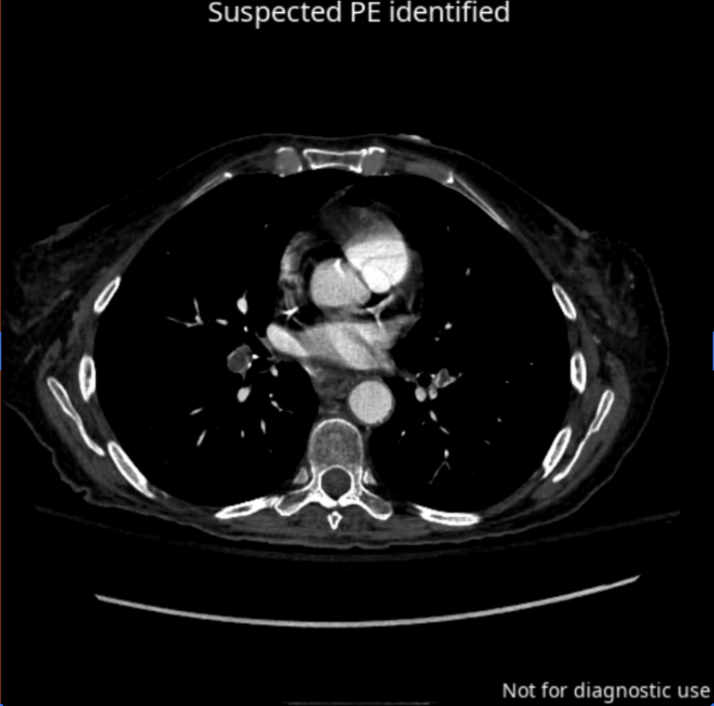

CINA iPE

Avicenna

CINA-iPE is radiological software for triaging suspected pulmonary embolism on chest CT angiography.